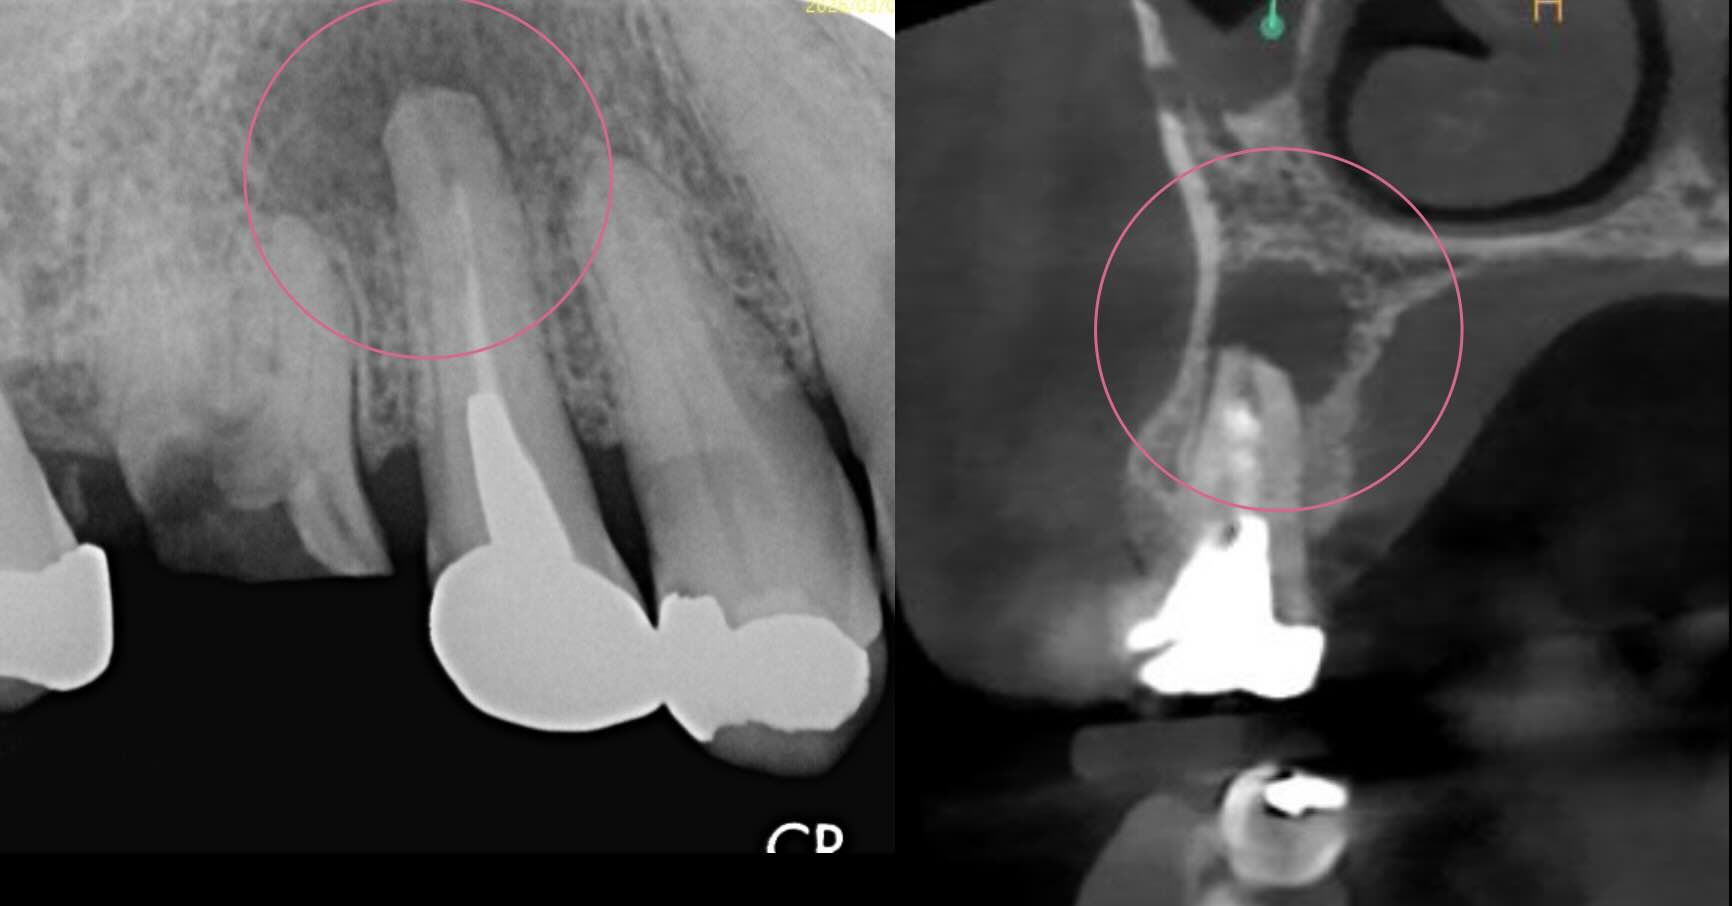

治療前

| 診断名 | pulp diagnosis : Previously treated periapical diagnosis : Acute apical abscess |

| 治療の方法 | 歯根端切除術(右上5番) |

| 治療の説明 | 急性症状があり、腫れているため、切開排膿。 2週間後に、opeの運びとなった。